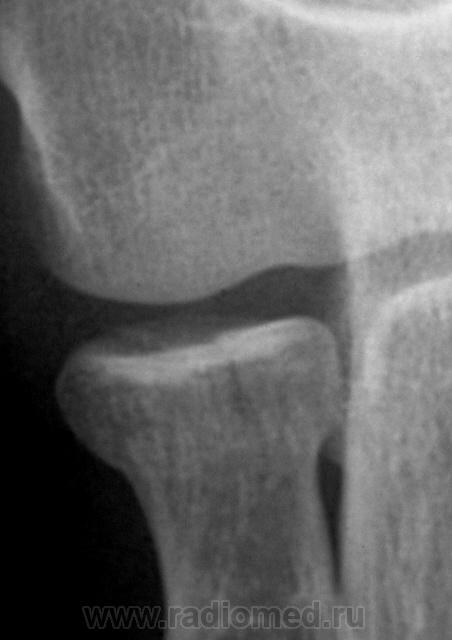

Боковая проекция.

Фрагменты с увеличением.

Предположу продольный перелом головки луча с допустимым смещением.

Хочется услышать мнение коллег по поводу "жировых подушечек". Как они, среагировали или нет?

Вот два Ваших случая Валентин Львович в первом случае внутрисуставной перелом с гемартрозом ну и соответственная картина, а во втором случае гемартроза нет. Поправьте меня, если я шось неправильно рисанулsmiley

Только думаю, что субстрат их все - таки гемартроз...

Следовательно, "отклонение" жировой ткани в виде образования "жировых подушечек", не свидетельствует, как утверждают многие, прямо, именно, о переломе, а свидетельствуют только о гемартрозе?

А, вот если, в полости сустава (гемартроз) будет не кровь, а другая жидкость, конечно, в достаточном количестве, получим мы на рентгеновском снимке феномен "жировых подушечек"?

Мое заключение чисто логическое - думаю это уровень гравитационного расслоения крови. Если другая жидкость будет состоять из неоднородных фракций разного веса - будет расслоение... А феномен будет в любом случае жидкости в суставе